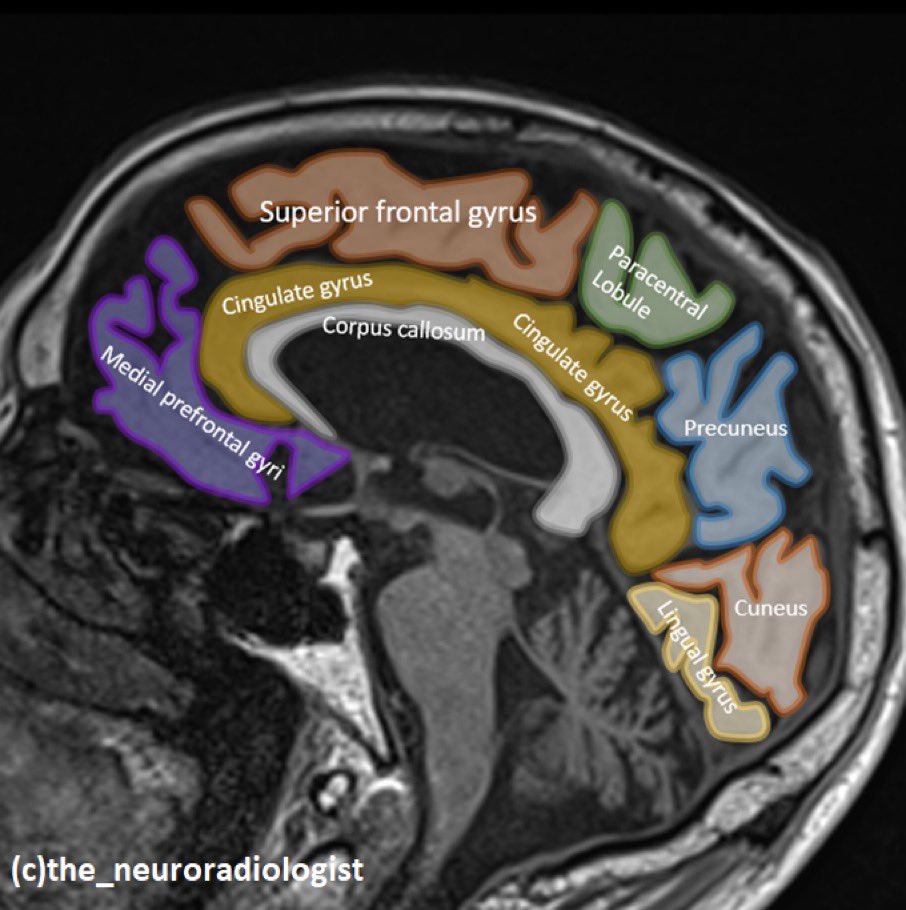

🤿🧠MRI features of Inflammatory Cerebral Amyloid Angiopathy (version 1.0) 🔑 👇🏿 #neurotwitter #NeuroTwitter #NeuroRad #MedTwitter #MedStudentTwitter #MedEd #EndNeurophobia #Neurology #Neurosurgery #RadEd #stroke Gregoire Boulouis World Stroke Academy

🤿🧠MRI features of Inflammatory Cerebral Amyloid Angiopathy

(version 1.0)

🔑 👇🏿